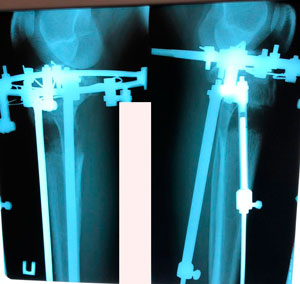

Исходник - 25 лет.

Диагноз: варусная деформация голеней. Удлинение голеней на 2 см (с целью увеличения роста)

Дата операции - 10.07.2019г.

рентген в процессе удлинения